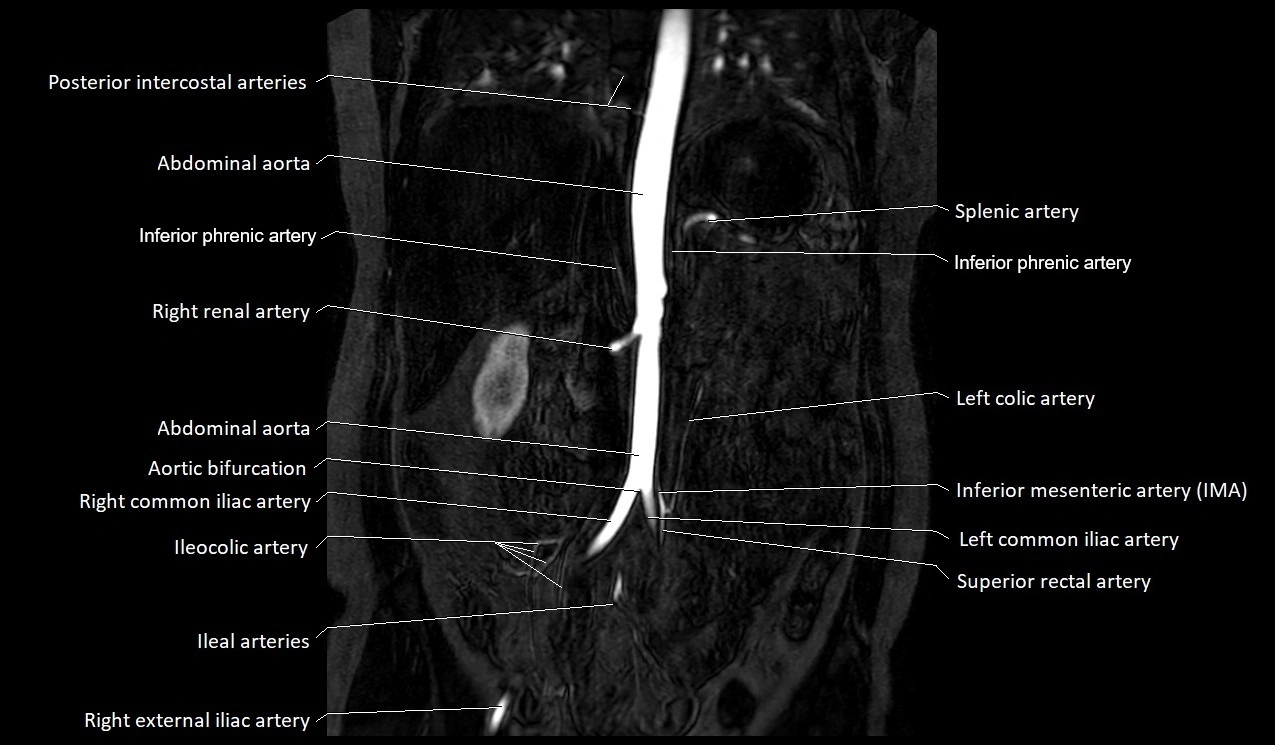

MRA Pelvis with Gadolinium:

-

Clearly delineates the origin, course, and anastomoses of the accessory obturator artery

Identifies connection with inferior epigastric artery, external iliac artery, or obturator artery

Excellent for detecting vascular variants prior to surgery

Useful in mapping pelvic vasculature in trauma, tumor embolization, or preoperative planning